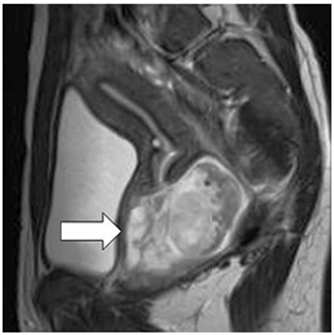

La tomografía computarizada abdominopélvica confirmó las características de la tumoración observadas en la ecografía. Las imágenes de resonancia magnética mostraron tumor sólido heterogéneo, bien definido, de 8 centímetros de diámetro, con varios tabiques levemente engrosados, y cambios quísticos, que se originaba en la parte superior de la vagina, con señal de baja intensidad en las imágenes ponderadas en T1 y de alta señal en las imágenes ponderadas en T2. Los órganos adyacentes, así como los planos de grasa pélvico/perineal, estaban bien conservados. El útero y el cuello uterino estaban aparentemente normalmente (figura 2). No se observaron adenopatías regionales. Las imágenes de tomografía computarizada de tórax eran normales.

El rabdomiosarcoma urogenital tiene una presentación clínica que varía según la localización del tumor. Sangrado, tumoración palpable, leucorrea y alteraciones urinarias o evacuatorias son los síntomas más comunes. El hallazgo más frecuente en el rabdomiosarcoma vaginal es el sangrado, mientras que los tumores vesicales pueden manifestarse principalmente con síntomas urinarios (9). La radiología convencional no es útil para el diagnóstico del rabdomiosarcoma. La ecografía se considera el primer método de evaluación porque permite visualizar masas heterogéneas, bien definidas y con flujo sanguíneo elevado (11). La resonancia magnética, por otro lado, ofrece una caracterización más detallada del tejido, generalmente mostrando una intensidad de señal intermedia en secuencias T1 y alta en secuencias T2, y con frecuencia presenta un aspecto quístico multiseptado debido al estroma mixoide (12,13).